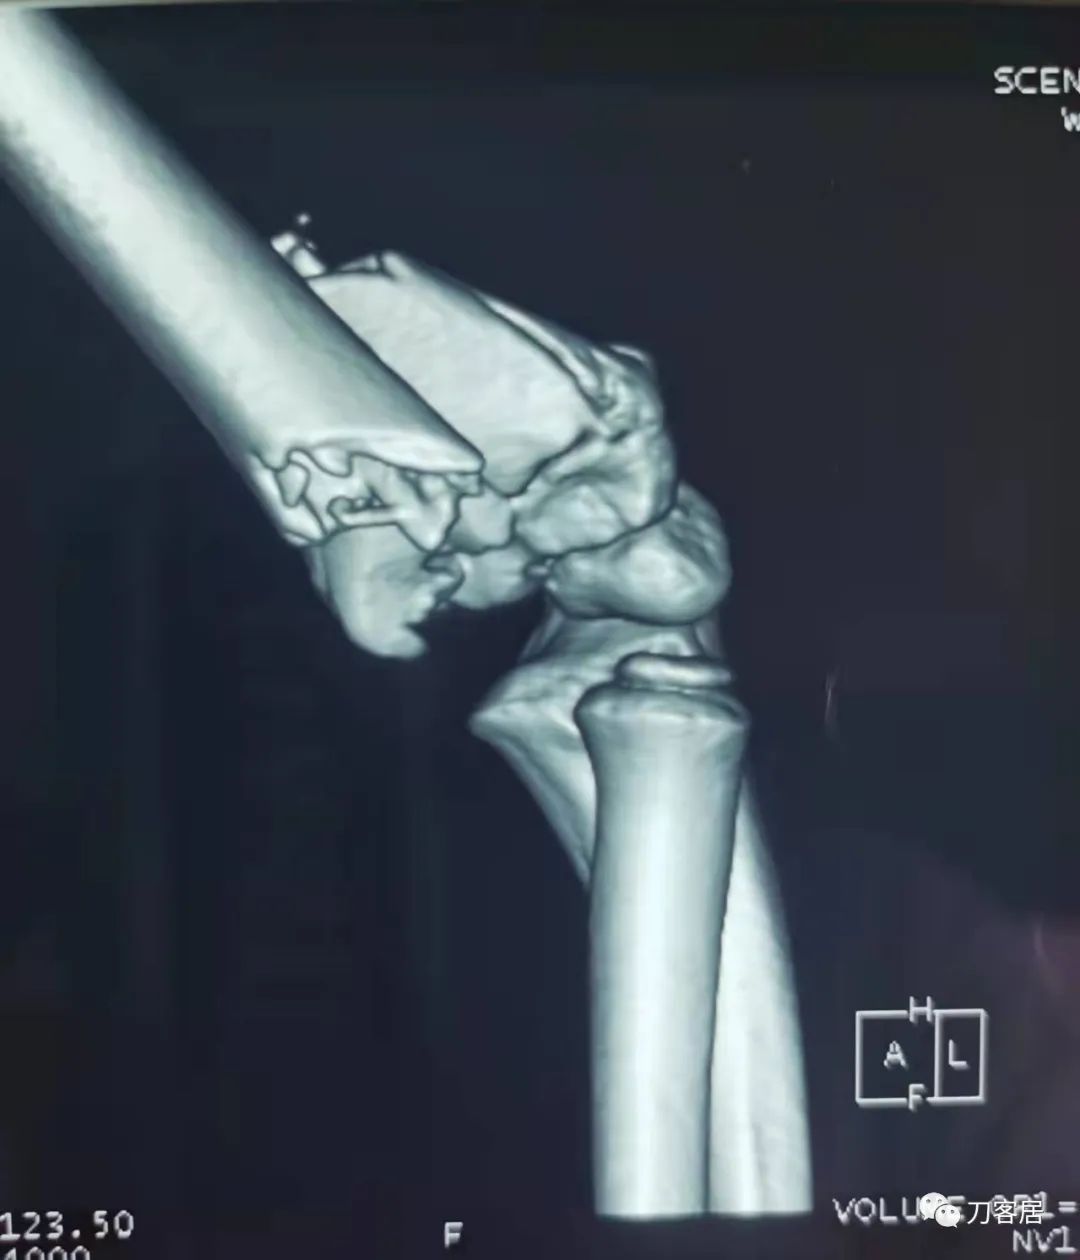

查体:左侧肘关节肿胀明显、疼痛、畸形,局部可见明显青紫瘀斑,左肘关节活动受限,肱骨远端环形压痛(+),局部可及异常活动及骨擦感形成,左上肢末梢桡动脉可触及,左侧腕关节及拇指背伸活动受限,左侧虎口区感觉麻木。辅助检查:自带X线及CT片示:左肱骨髁间粉碎性骨折。

入院诊断:1. 左肱骨髁间粉碎性骨折;2.左肱骨远端骨骺损伤;3. 左桡神经损伤。

20210922当地省中医院三维CT01

20210922当地省中医院三维CT03